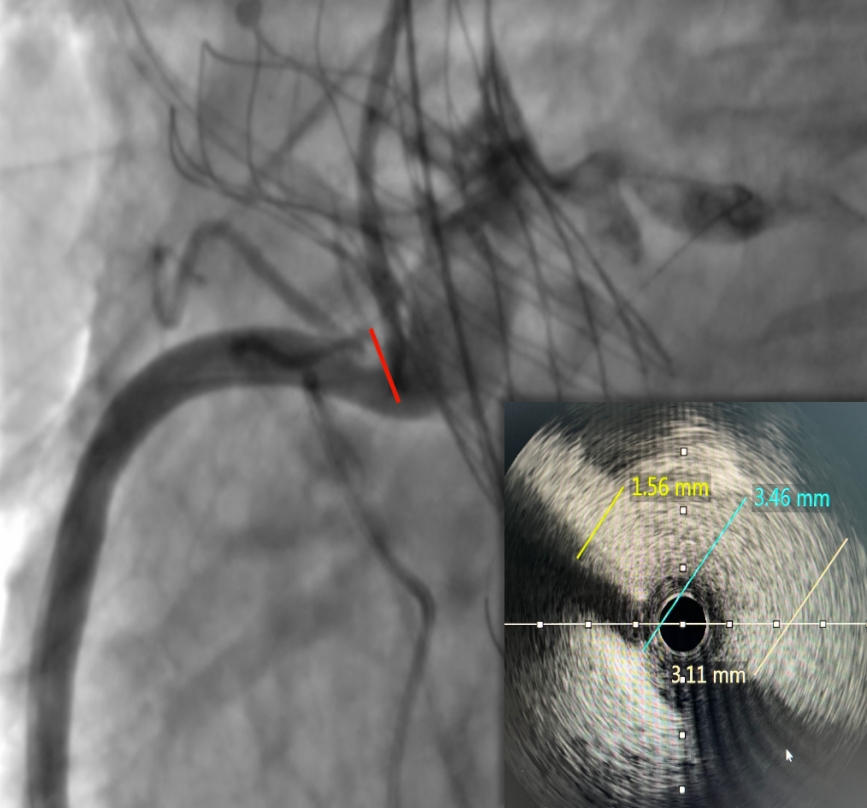

右冠开口残余1.56mm-3.46mm,血流无明显阻挡。